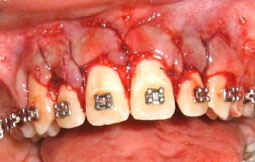

1er cas clinique :

![]() |